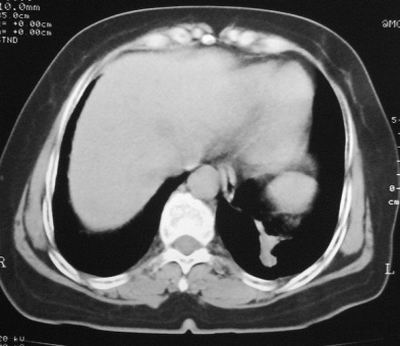

患者,女,64岁,4年前左腮腺"多形性"腺瘤手术治疗史.现复查胸部ct见左下肺块状影,该影与原左腮腺手术是否有联系?

本次复查胸部ct

左下肺后基底段实性肿块,周围有毛刺,病变周围有肺气肿,与降主动脉间有条带状影相连,病灶4年前查体发现,纵隔内未见肿大淋巴结。考虑.肺隔离症,建议增强扫描与周围型肺癌鉴别。